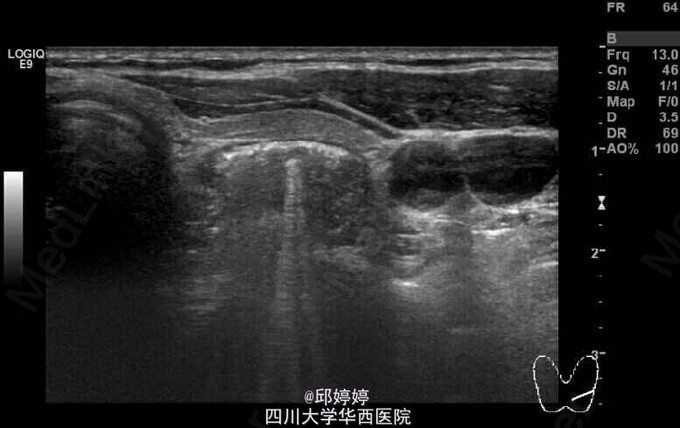

患者,女,60岁,无特殊不适,行常规体检。超声检查发现患者颈部甲状腺左侧叶后方查见大小约23x9mm的杂乱回声团,内可见气体样强回声,后方回声衰减(图1-3)。 诊断:食管憩室。 此种现象较为少见,应注意与甲状腺本身的病变相区别,以防误行进一步的穿刺活检而导致食管损伤。